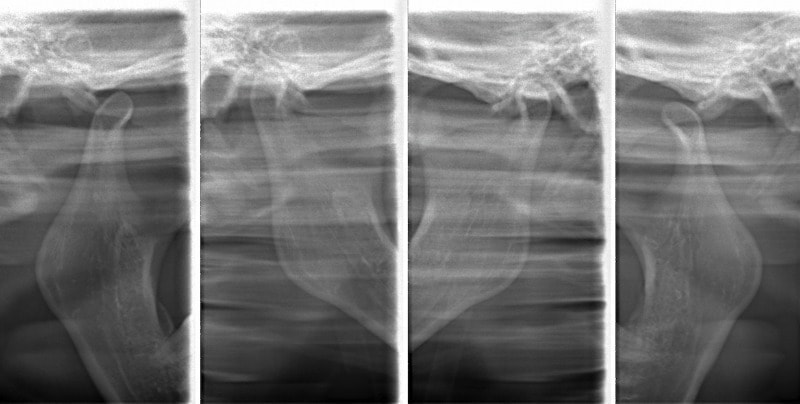

治療後顎関節レントゲン

CO-CR位置の改善が認められます。